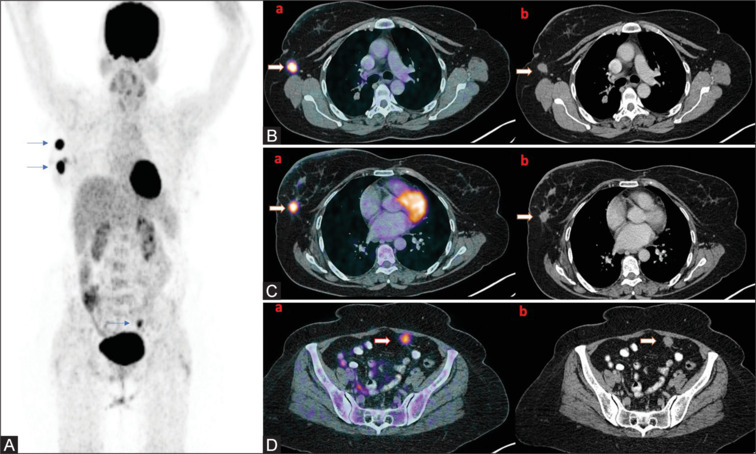

We present an unusual case of invasive ductal breast carcinoma in a postmenopausal female with a clinically node-negative disease that was incidentally found to have mesenteric metastatic deposits on 18F-fluorodeoxyglucose positron emission tomography/computed tomography scan. Mesenteric metastasis from invasive breast carcinoma is rare, with <1% cases reported worldwide and limited availability of diagnostic and therapeutic protocols for carcinoma breast with mesenteric metastasis, this proved to be a challenging and intriguing case. To further accentuate the complexity, the primary tumor of this mesenteric metastasis was found to be invasive ductal carcinoma, which is even more infrequent, and <0.5% of cases have been reported till date.